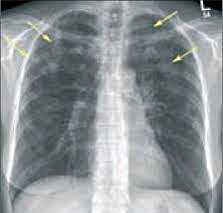

- Рентгенография легких. На снимках видны субплеврально расположенные одиночные (реже множественные, двусторонние) нечеткие затемнения средней интенсивности неправильной формы размером до 3-4 см. В окружении инфильтрата легочный рисунок усилен, тень корня легкого слегка расширена. Характерна быстрая динамика инфильтратов с миграцией по легочным полям и исчезновением не позднее 1-2 недель после обнаружения (чаще через 1-3 дня) без остаточной рубцовой деформации. При длительно поддерживающемся инфильтративном воспалении в ткани легких могут образоваться фиброзные очаги и кистозные полости.

- Рентгенологические исследования. Одним из наиболее информативных методов диагностики легочных эозинофилий считается рентгенография грудной клетки. На снимках обнаруживаются летучие (мигрирующие) эозинофильные инфильтраты в виде участков затемнения. При аллергическом бронхолегочном аспергиллезе могут быть видны бронхоэктазы, фиброз верхних отделов легких.